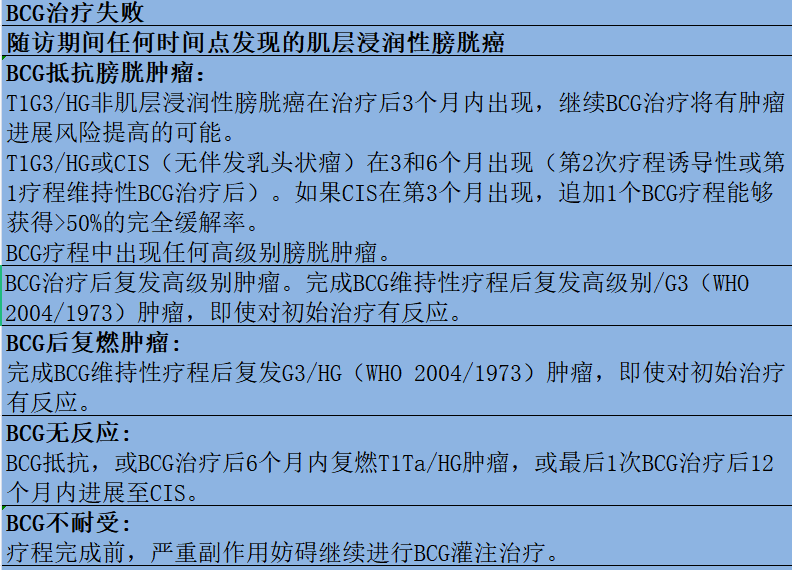

BCG治疗期间或治疗后复发低级别肿瘤,不属于BCG治疗失败。

BCG膀胱灌注治疗失败病例分类: